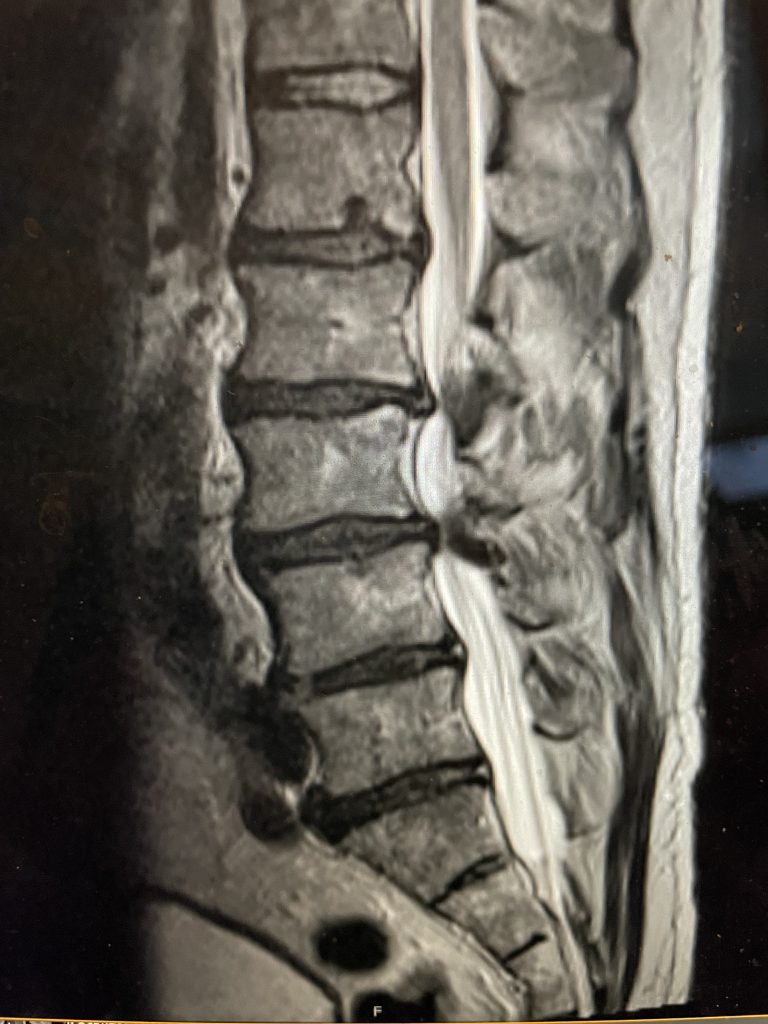

Figure 2. Axial T2-weighted MRI demonstrating severe concentric stenosis at L3-4 due to severely enlarged facet joints and ligamentous hypertrophy

MRI demonstrated severe L3-4 stenosis with a grade 1 spondylolisthesis. He also had L2-3 stenosis. (Fig 1). On axial MRI (Fig 2) he had severe concentric stenosis at L3-4, but on careful examination it appeared that the right side had particular distortion of the anterior aspect of the thecal sac, perhaps secondary to a facet cyst. It seemed more likely coming off the facet joint and not a disc herniation. Although the right side was worse, most of his symptoms were on the left. Why does that happen? I don’t have a great explanation. Clearly the left side is also compressed but sometimes the body just chooses the side to be affected symptomatically when both sides are involved. This is true for compression of the spinal cord for instance in the cervical spine. What is not right, however, is that if a patient has a lateralized disc herniation and the opposite side is symptomatic and without compression, then one should not offer surgical treatment unless that disc is causing severe compression on one side with just less compression on the ipsilateral symptomatic side. Then one can argue that the pathology is having an effect on the opposite side if there is some degree of bilateral compression even if the ipsilateral symptomatic side is less compressed.